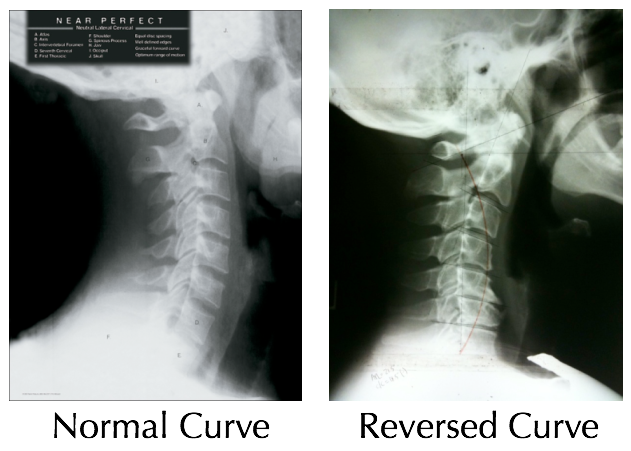

I did eventually, about 6 weeks after the fall, go to my doctor, who had xrays done. He reported that nothing was broken, but I do have a “reversal” in my neck. This is where the spine in the neck reverses its curve. Its not uncommon and although my doctor speculates it was caused by my fall, it is something that some people just have normally. He prescribed muscle relaxers and physical therapy.

(this image is stolen from google images and is not of my particular neck, but shows what is going on in my neck).